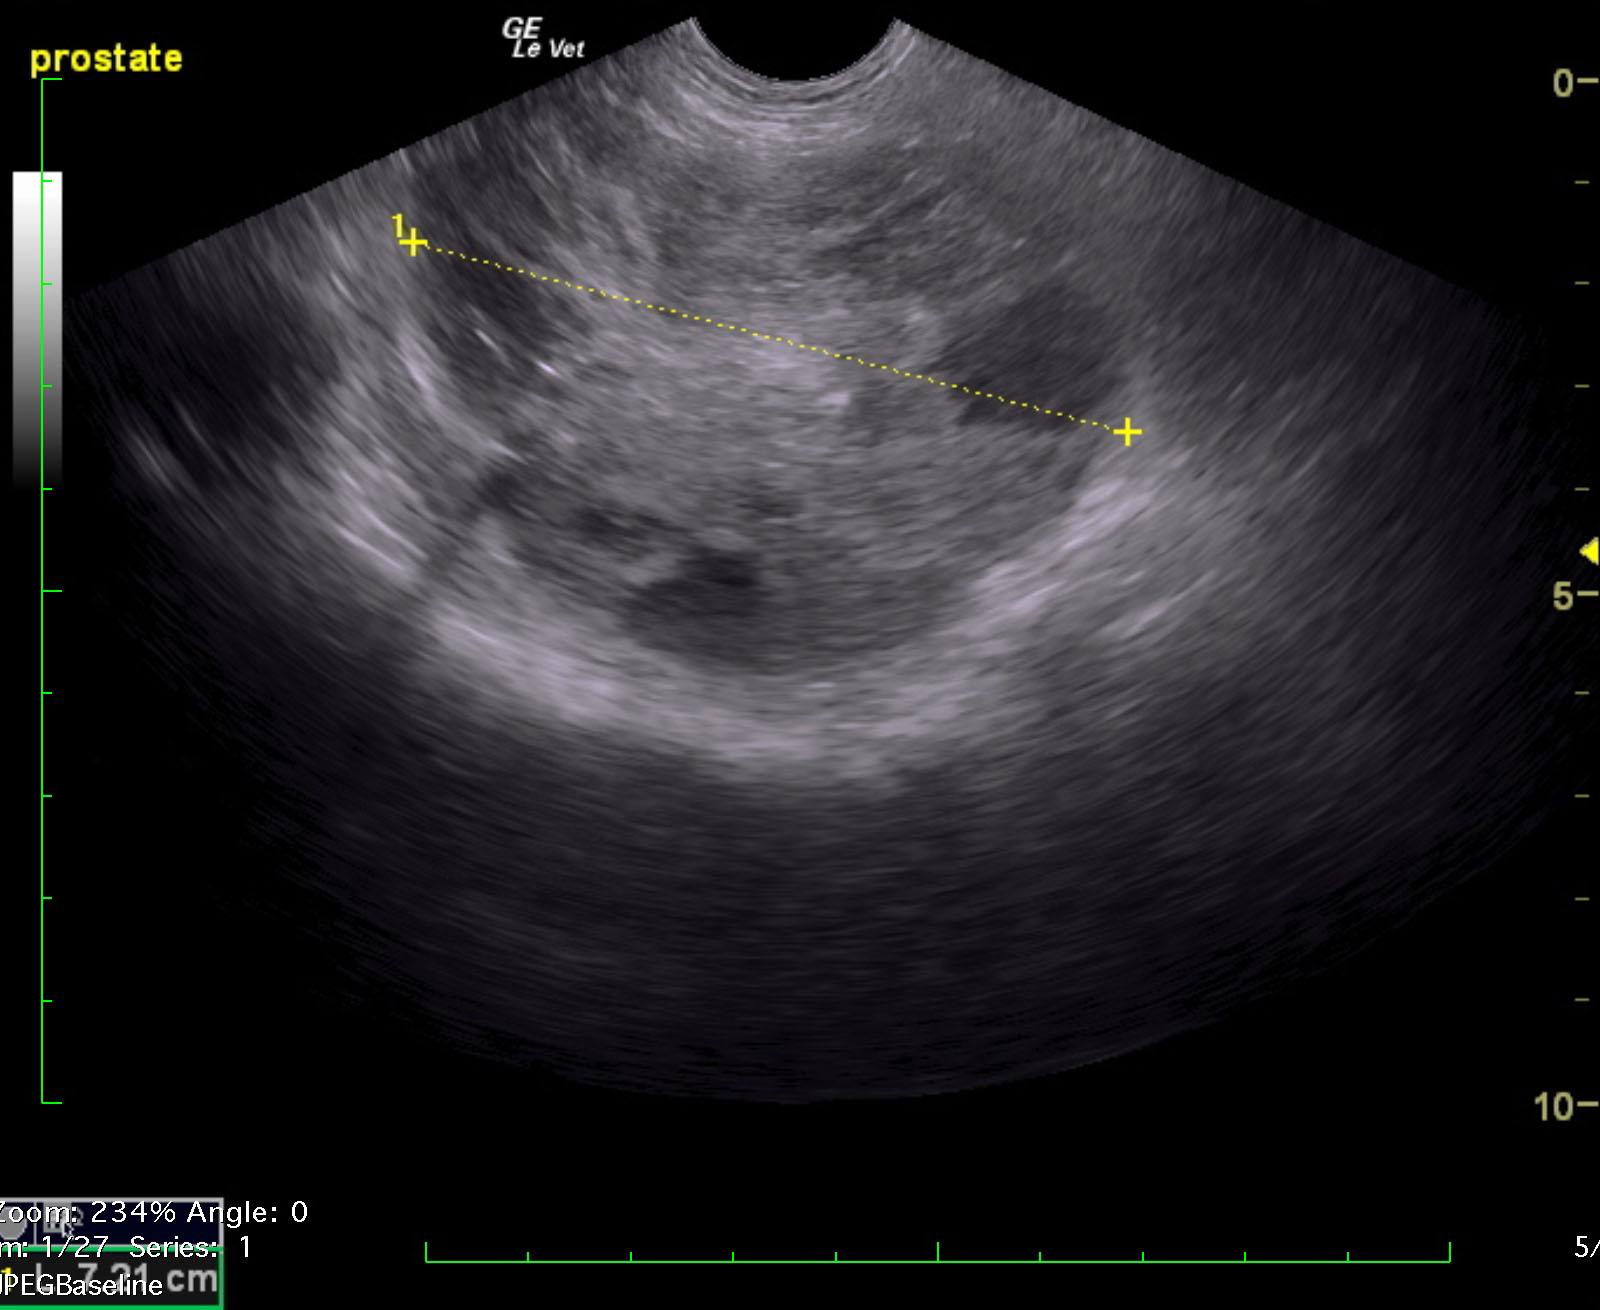

A 10-year-old intact male Komodor with a history of bleeding from the penis was presented recumbent and dyspneic. Abnormalities on CBC and serum biochemistry were leukocytosis, band neutrophilia, monocytosis, azotemia, mild hyperglobulinemia, mildly elevated liver enzyme activity and hyperbilirubinemia.